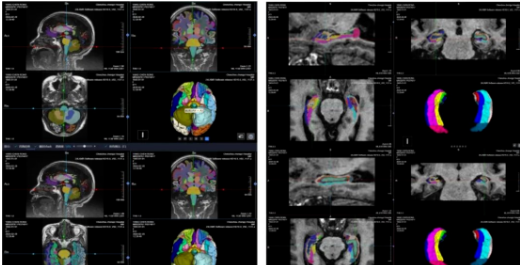

▲杨奶奶脑健康评估报告部分图示